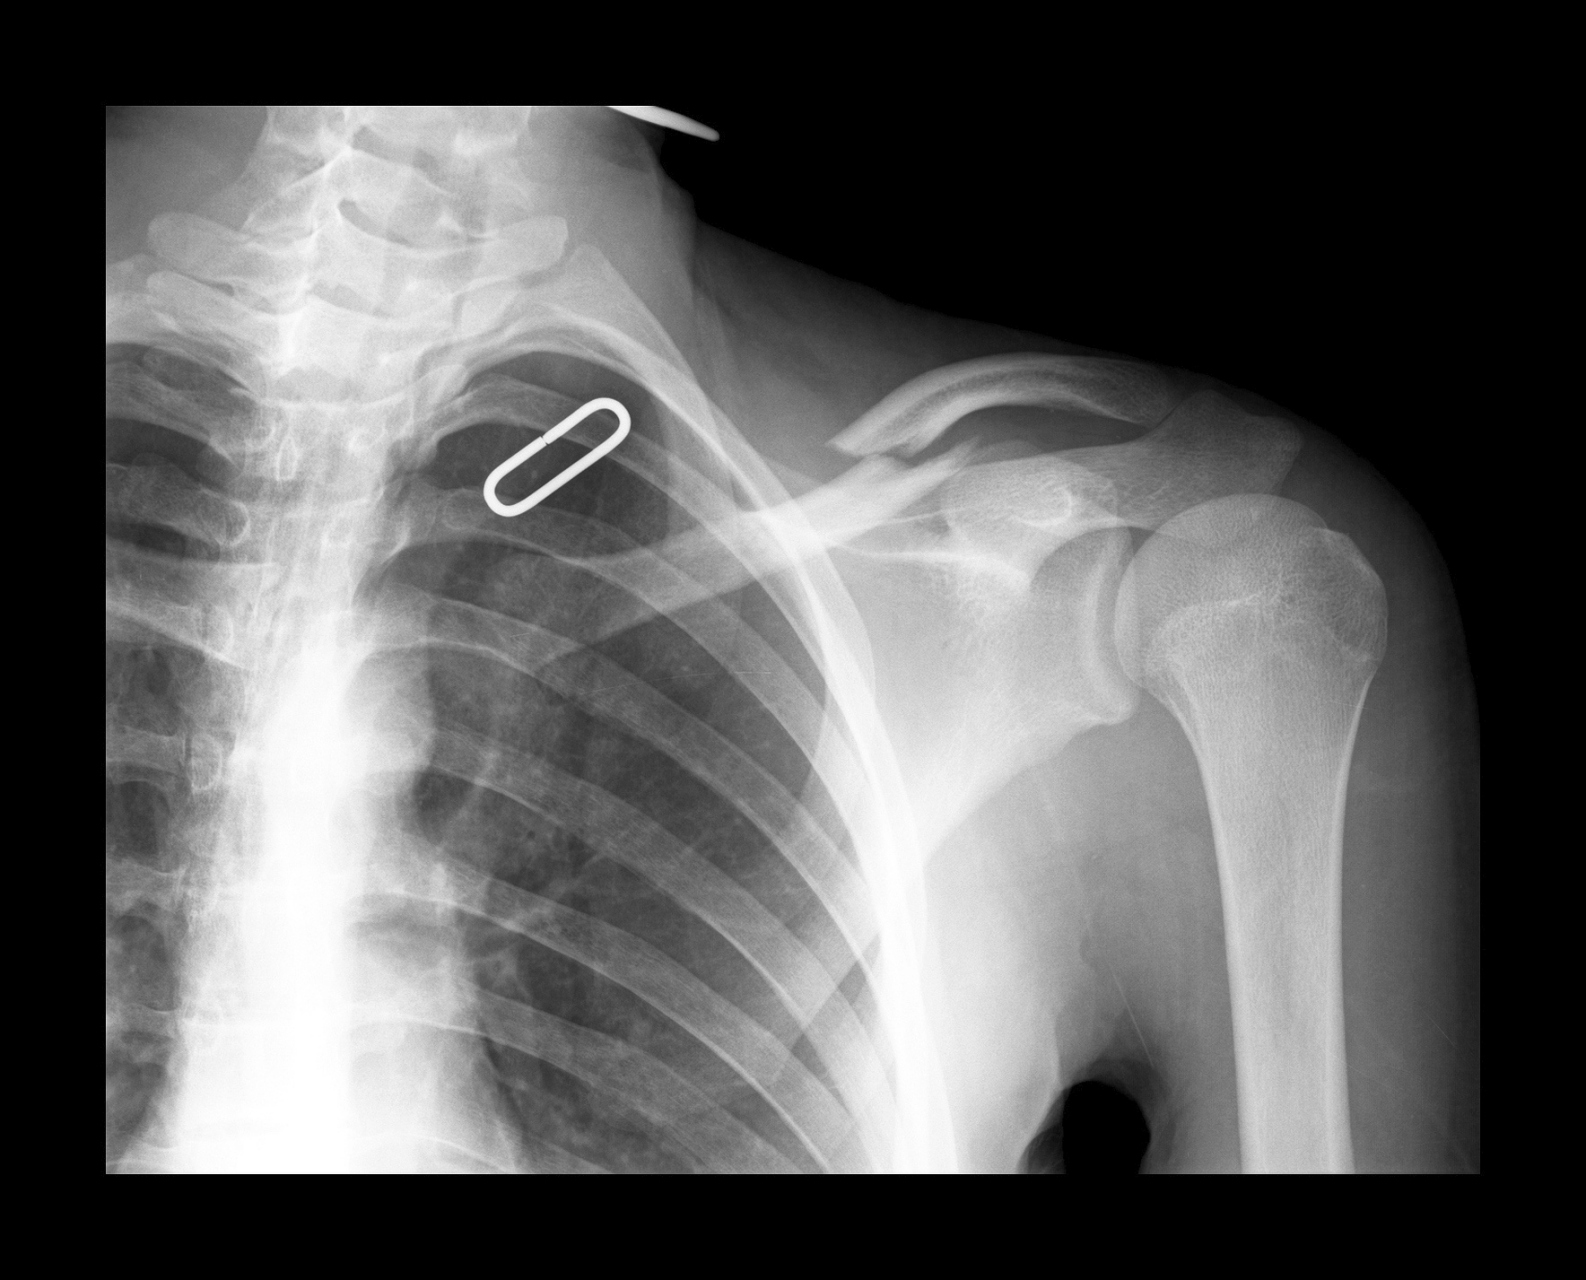

左肩x线片

肩胛骨骨折一例

写美篇这个病例提醒我们,肩部背部外伤要注意肩胛骨,肩关节正位不宜